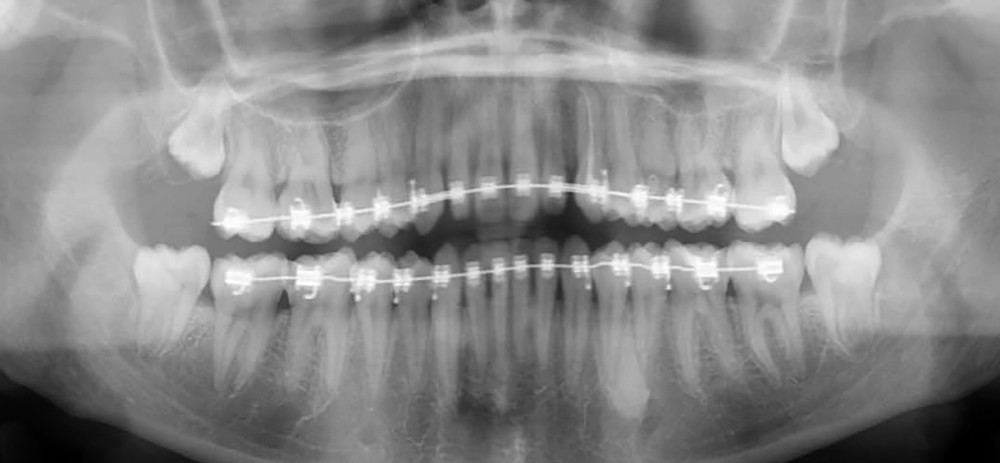

Le traitement orthodontique a été réalisé en technique vestibulaire multi-attaches 0,022’’ x 0,028’’. Après l’alignement et le nivellement de l’arcade maxillaire (arcs Niti 0,014‘’,0,018‘’, 0,017 x 0,025’’), un acier 0,019 x 0,025’’ a été mis en place. Un ressort Niti actif a permis de créer l’espace nécessaire pour accueillir la 23 sur l’arcade (fig. 3). L’espace nécessaire a été évalué par mesure de la réplique dentaire tridimensionnelle.

Auto-transplantation

Une fois l’espace nécessaire obtenu, des cales molaires sont réalisées pour limiter les interférences occlusales avec la 23. La 63 et l’odontome sont extraits (fig. 4). Un lambeau est levé et la réplique 3D de la 23 est essayée dans l’alvéole, qui est adaptée en fonction (fig. 5). La 23 est prélevée de façon atraumatique (fig. 6) et auto-transplantée (fig. 7). Après suture du lambeau (fig. 8), une contention par arc acier 0,019×0,025’’ avec un CVI entre la dent et l’arc orthodontique est réalisée (fig. 9). Trois ou quatre semaines après l’auto-transplantation (fig. 10), le traitement endodontique est effectué (fig. 11). Un bracket orthodontique pourra être collé de façon passive, et la dent prise en charge avec un arc Niti 0,017 x 0,025’’ (fig. 12).

Des radiographies rétro-alvéolaires de contrôle sont effectuées au cours du traitement, il est recommandé de ne pas entreprendre de mouvement orthodontique pendant 4 mois à l’arcade maxillaire.